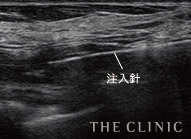

溶解液注入   的確にしこりへ穿刺・注入

-

溶解中   エコー下でしこりにアプローチし、確実に生理食塩水を注入